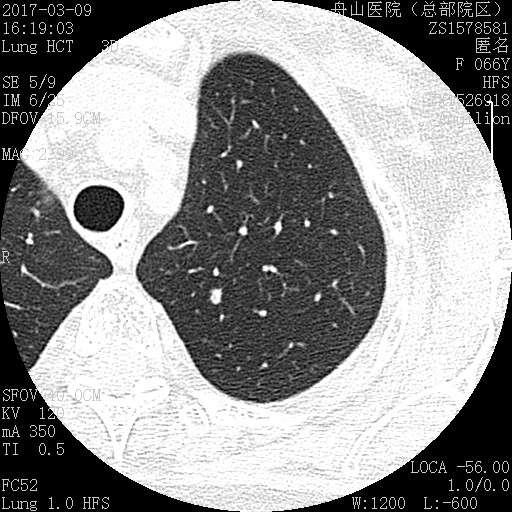

许多小白球--隐球菌,不做PAS及六铵银特染也看得清 荚膜的感觉明显 第三例的CT